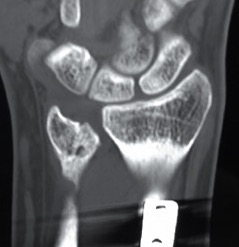

Bower's interpositional hemiarthoplasty

Technique

- best for young OA

- excision of arthritic portion through 5/6 compartment / hemiresection

- intact TFCC for interposition

Indications

- young OA

- not suitable in RA as TFCC damaged